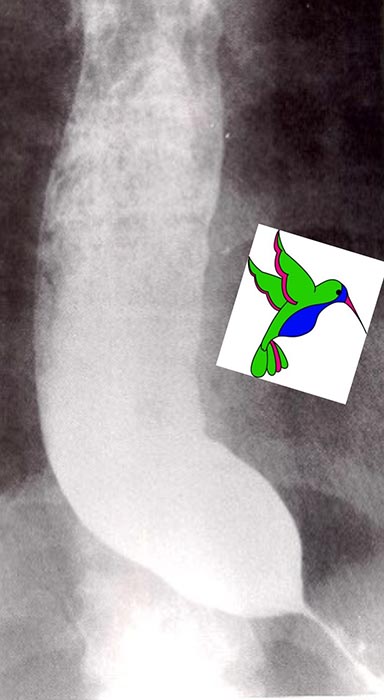

Bird’s beak sign, string sign, corkscrew esophagus.

What are the classic barium swallow signs of achalasia?